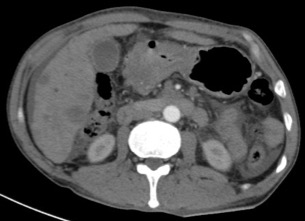

Gastric abnormalities show nonspecific gastrointestinal symptoms and similarly radiological findings. Intra and extra luminal gastric wall thickening are the most common finding in benign and malignant pathologic process. This aim of this case report was to describe several characteristics such as the location and size of the lesion, involvement of the gastric wall and surrounding structures, calcifications, and contrast enhancement pattern which can assist in radiological diagnosis. Several cases at our institution have similar gastrointestinal complaints, however, there were different lesions characteristic found in contrast enhanced abdominal CT scan. The first case 72-years-old man experienced hematemesis with radiologic finding diffuse gastric mucosal thickening as well as homogenous contrast enhancement but without calcification. The second case 37-years-old man complaint dizziness and melena with radiologic finding large tumor more than 10 cm in size, amorph calcification and heterogenous contrast enhancement. The last 60-years-old man case experienced melena and hematemesis, from abdominal CT scan showed irregular gastric mucosal thickening with heterogenous contrast enhancement and fat stranding around the lesion, without calcification. Methods used in these cases were contrast-enhanced abdominal CT scan, esophagogastroduodenoscopy (EGD), and biopsy in order to determine the diagnosis. Contrast-enhanced abdominal CT scan plays a vital role in describing the lesion characteristics which affects the determination of treatment options and future prognosis.